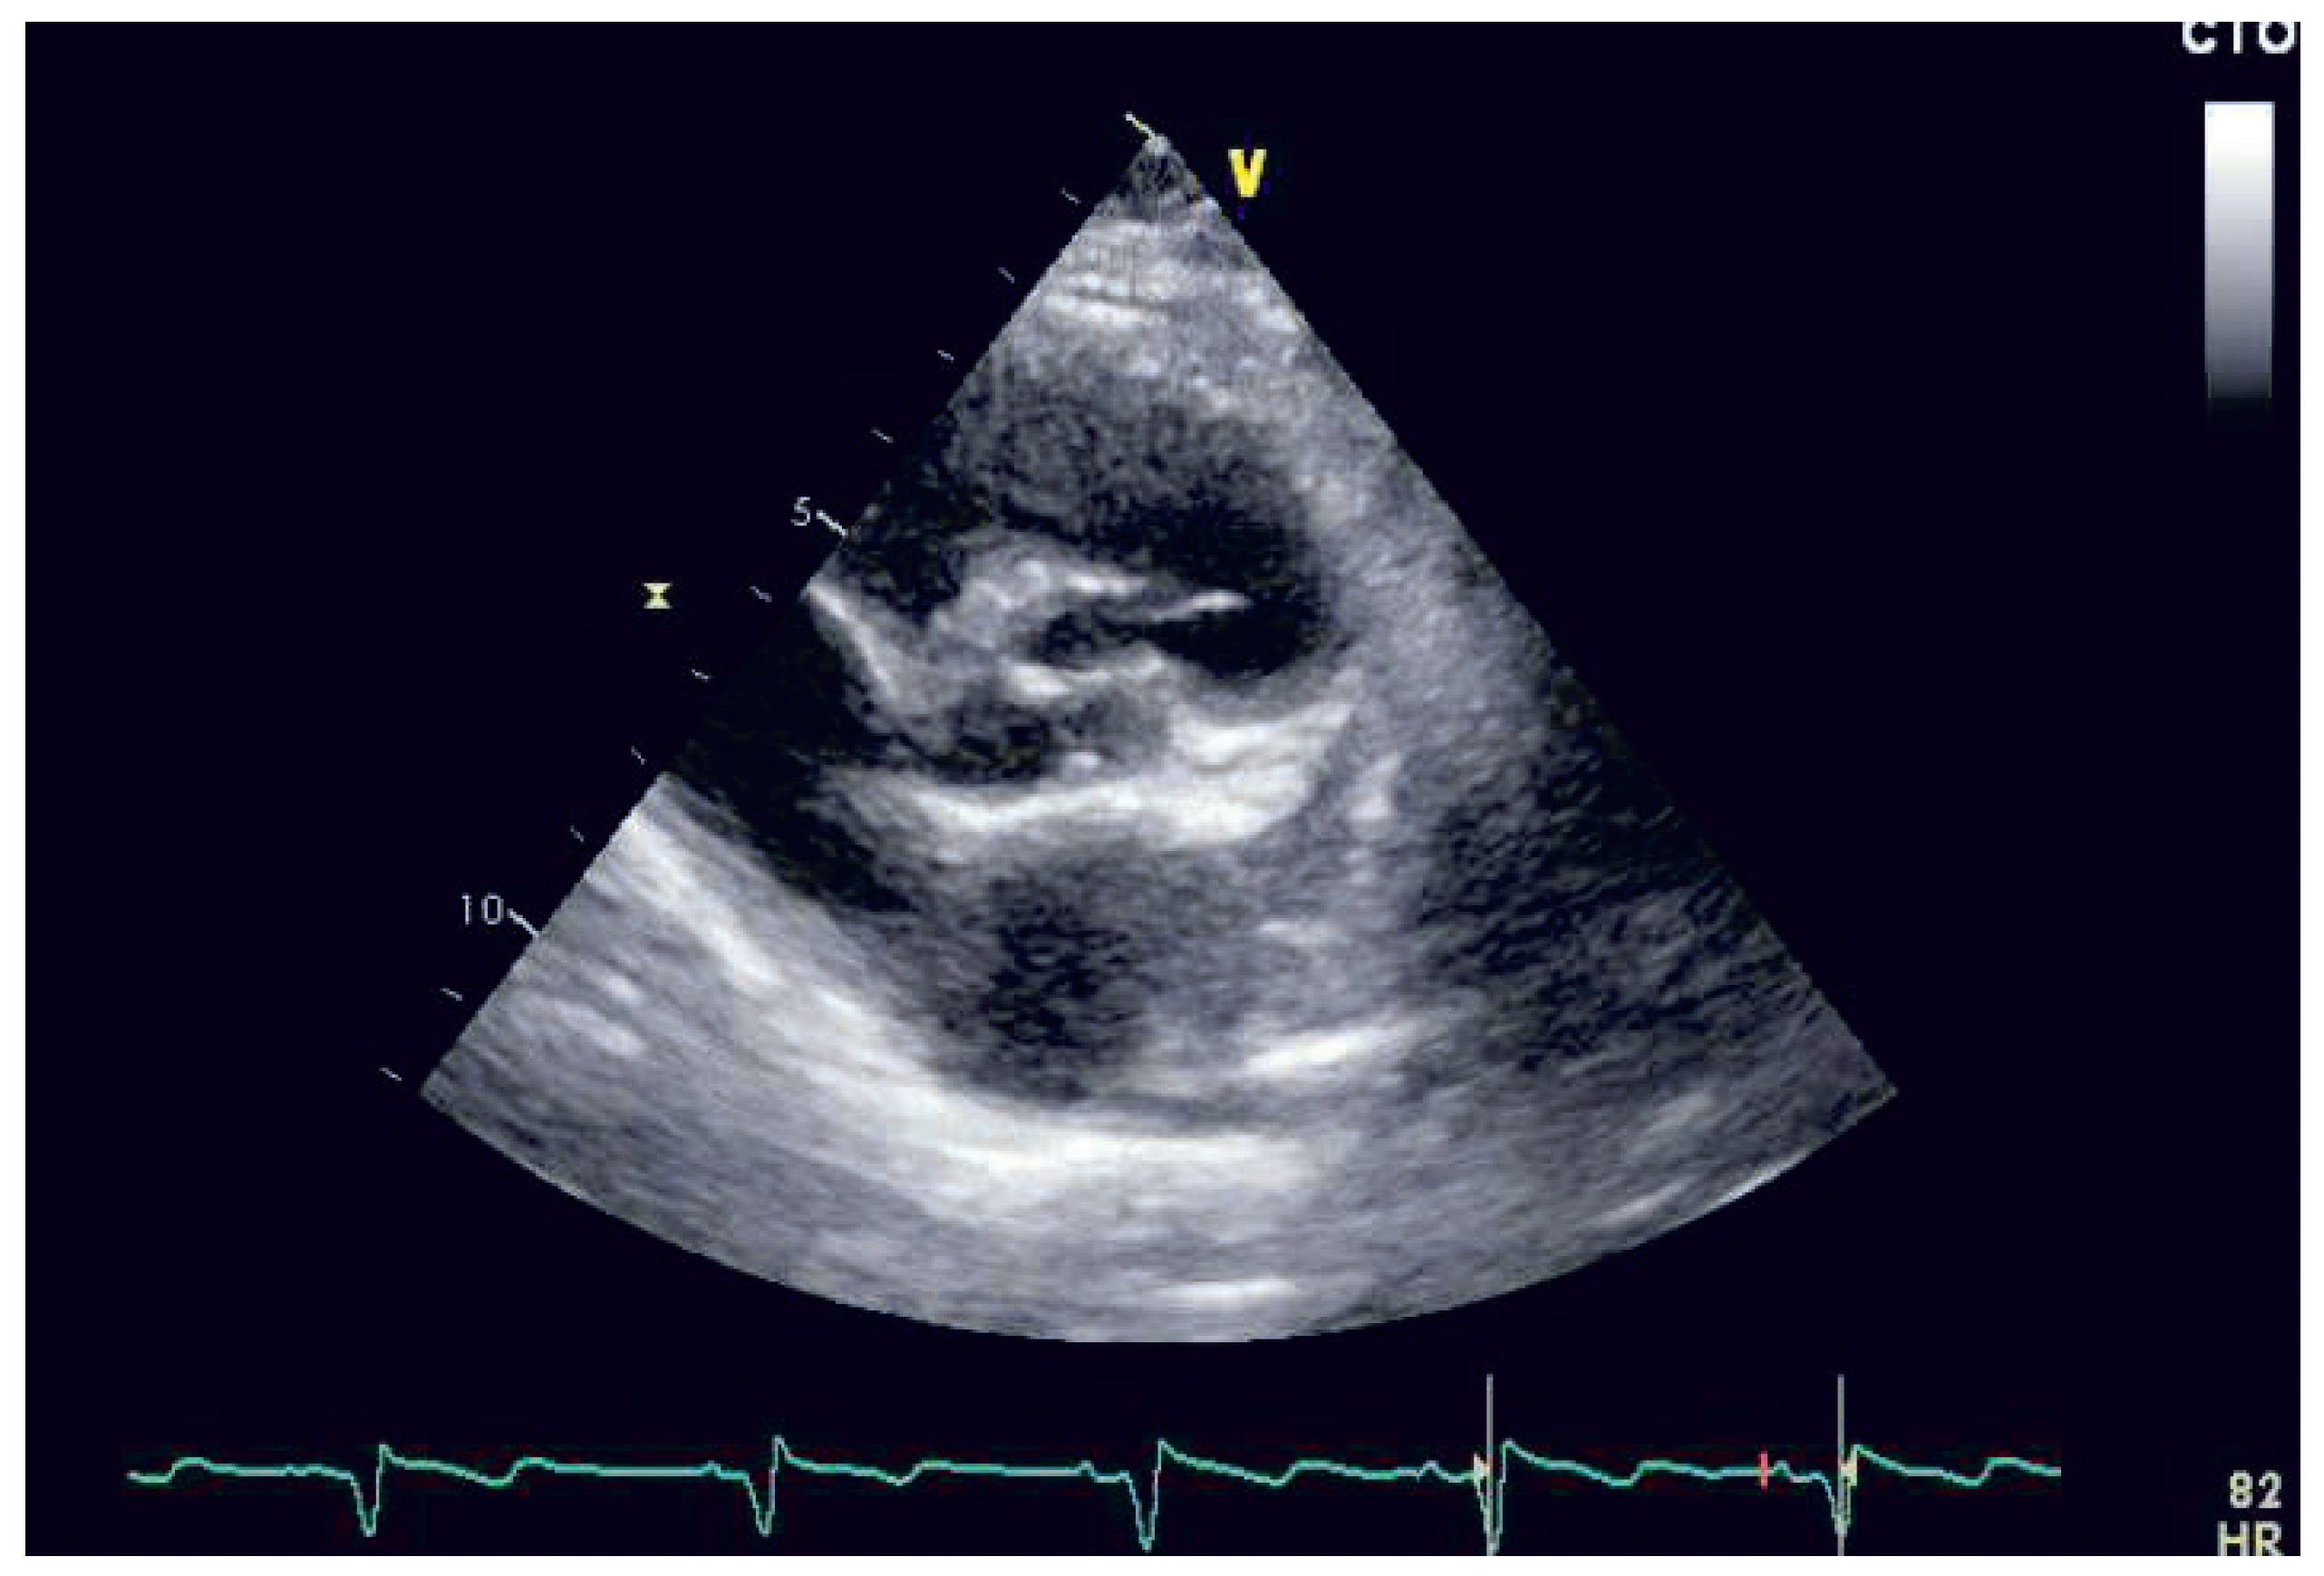

Case report